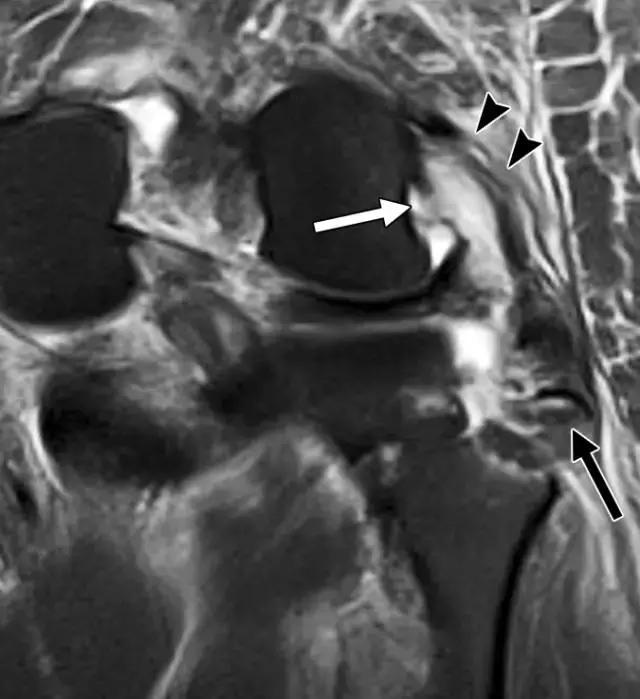

反向Segond骨折,是内侧胫骨平台的撕脱骨折,它是后交叉韧带严重受损的标志。这种骨折中的放射学检查结果与经典Segond骨折相似,只是反向骨折涉及胫骨近端的内侧(图6A)。据认为是由于内侧副韧带的深部荚膜组分的撕脱引起的(图6B),并且经常与内侧副韧带的严重损伤和相邻内侧半月板的周边损伤有关。

图6A -18岁的女性患有反Segond骨折。膝盖倾斜放射照片显示沿内侧胫骨平台的小撕裂性骨折(箭头)。

图6B,冠状脂肪抑制T2加权MR图像显示内侧胫骨平台内有明显的骨髓水肿,与内侧副韧带深部囊膜组分相关的反向Segond撕脱性骨折(箭头)。